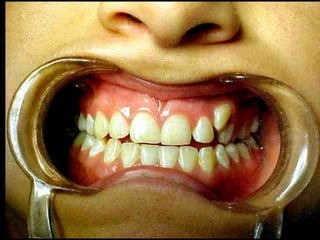

La periodontitis, denominada comúnmente piorrea, es una enfermedad que

inicialmente puede cursar con gingivitis, para luego proseguir con una pérdida de

inserción colágena, recesión gingival, e incluso la pérdida de hueso, en el caso de

no ser tratada, dejar sin soporte óseo al diente. La pérdida de dicho soporte

implica la pérdida irreparable del diente mismo.

De etiología bacteriana que afecta al periodonto (el tejido de sostén de los dientes,

constituido por la encía, el hueso alveolar, el cemento radicular y el ligamento

periodontal) se manifiesta más comúnmente en adultos mayores de 35 años, pero

puede iniciarse en edades más tempranas.